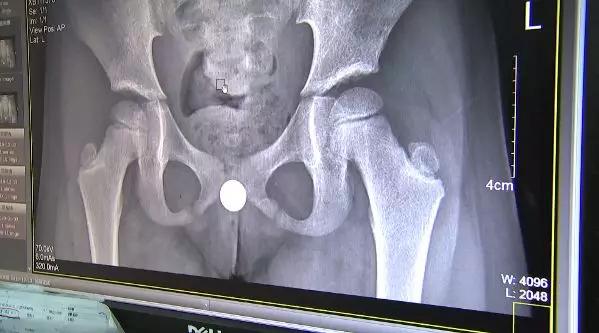

就这样过了3、4天,女孩肚子越来越痛,连走路都有点不大对劲了,医生一检查,发现小姑娘下身有异物。

沈医生说,女孩*体下**有一个纽扣电池,后遗症还是比较严重的,女孩阴道里面大片烧焦,因为已经3、4天过去了,有一些已经变成了一个疤痕。

纽扣电池在体内烂掉了,引发肚子痛,医生连夜做手术将已经发黑的电池取了出来。小姑娘说,电池是自己玩的时候塞进去的。